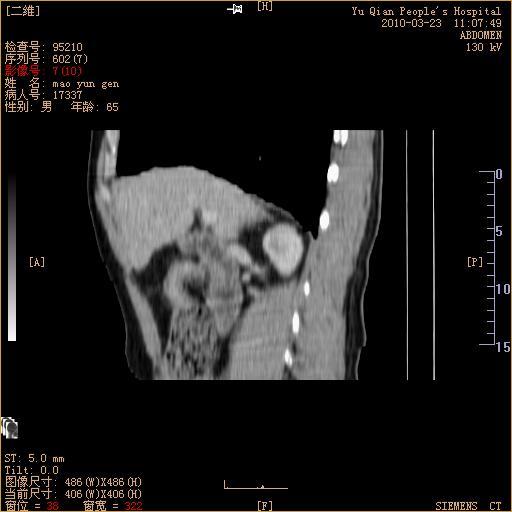

标题: CT25266:消瘦月余,前来肝部检查,请看看肠腔 [打印本页]

标题: CT25266:消瘦月余,前来肝部检查,请看看肠腔

肝区结肠占位,腺癌可考虑,建议肠镜活检。

升结肠肠壁增厚,不均强化,考虑升结肠腺癌可能性,建议肠镜检查。

1)考虑升结肠癌。2)右肾小囊肿。